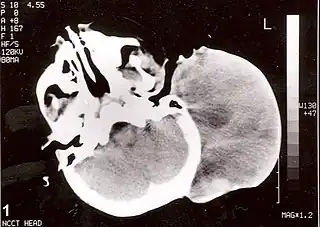

![]() Tomografía axial computarizada sin contraste de la cabeza, que muestra una gran masa sin extensión intracraneal. El diagnóstico fue de rabdomiosarcoma alveolar congénita post auricular. | ||